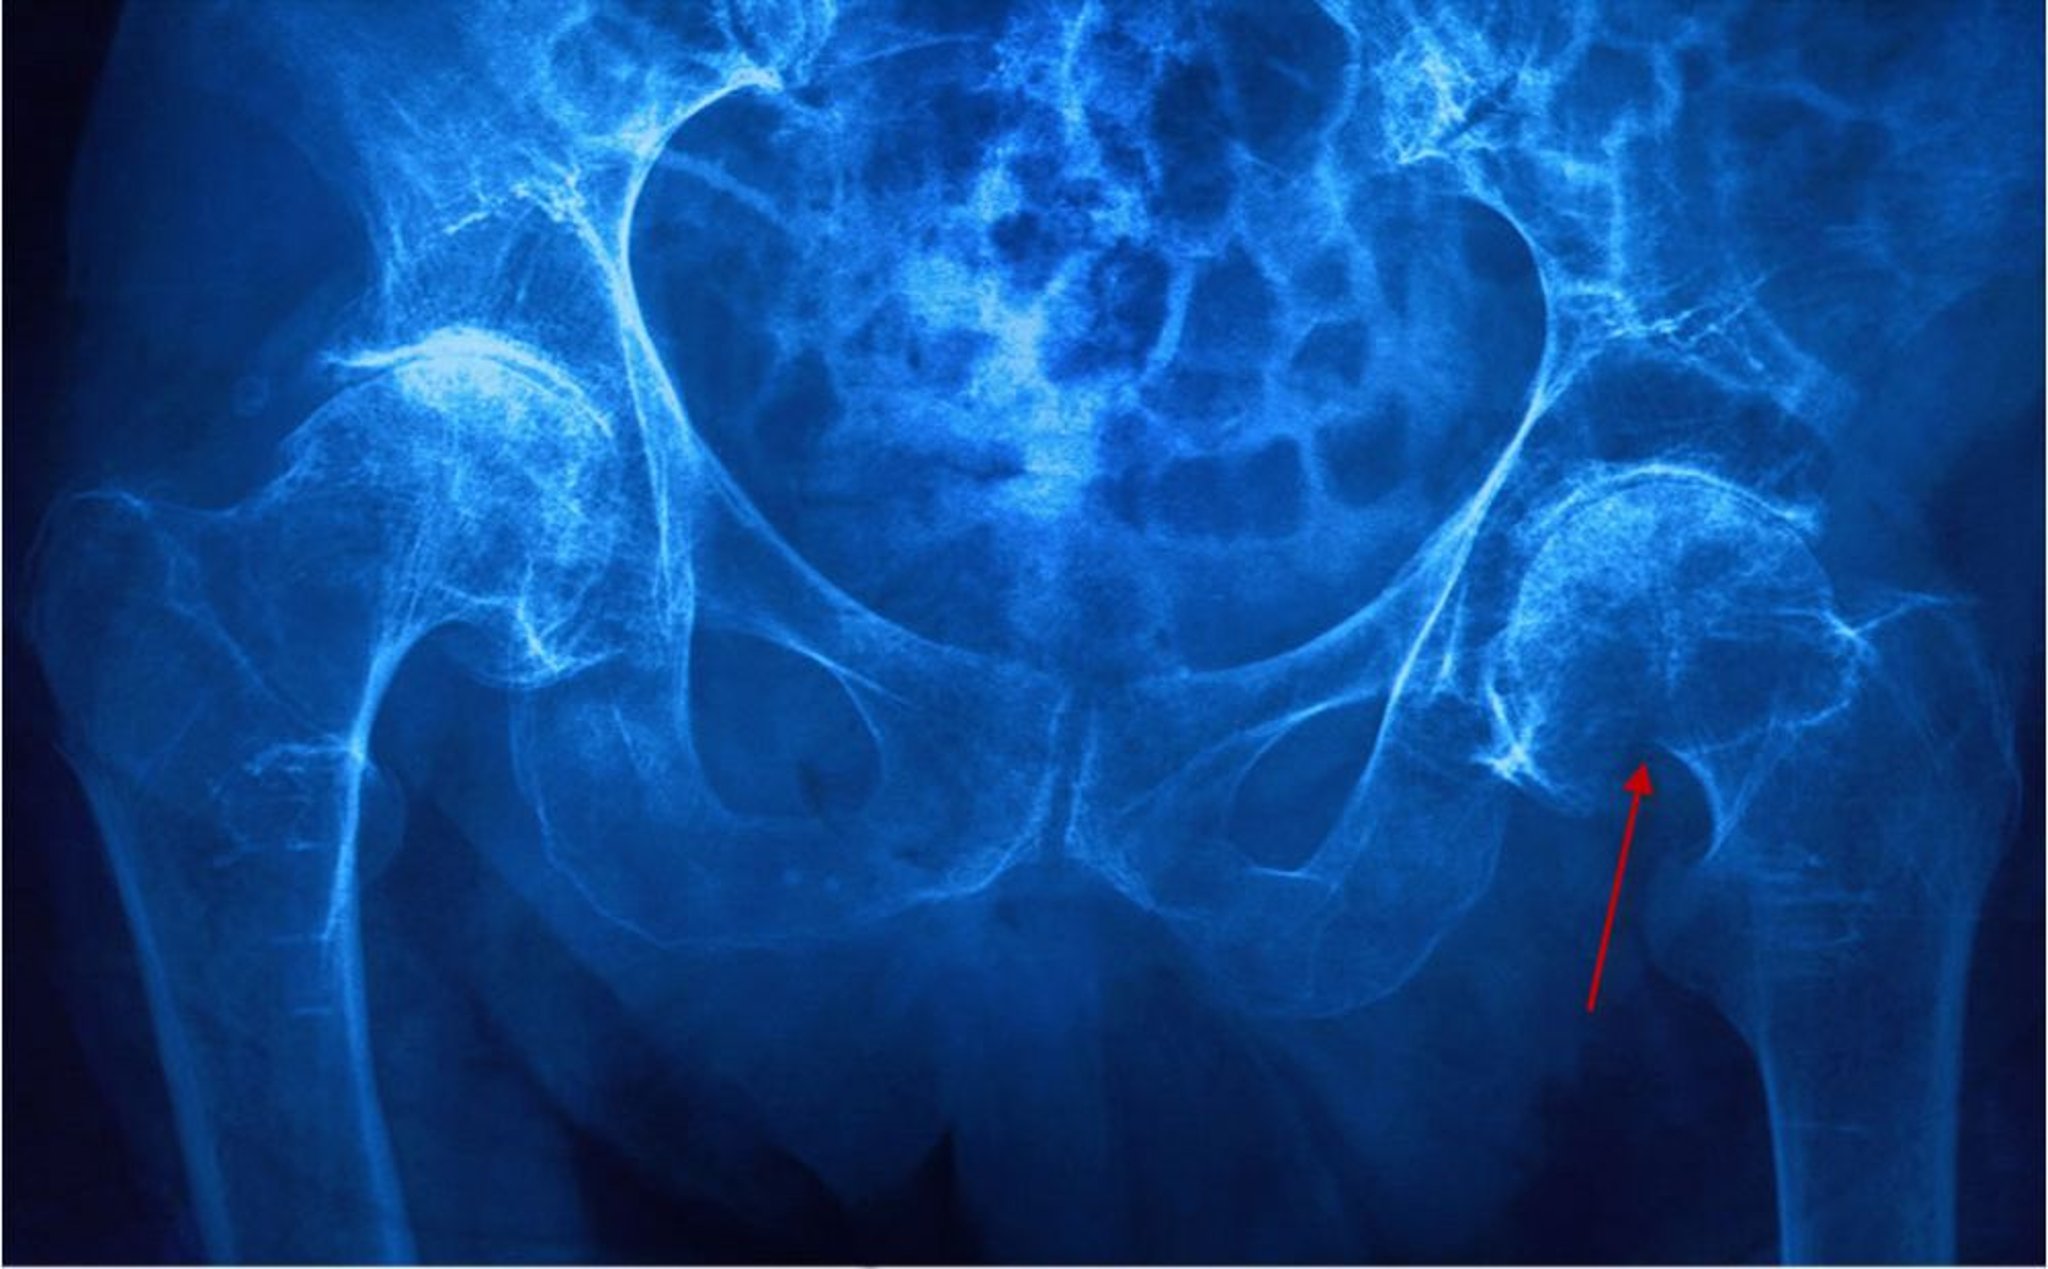

Fracture du col du fémur

Cette radiographie montre une fracture du col fémoral gauche (sous-capitale) mise en évidence par un col fémoral raccourci et une rupture de la corticale (flèche).